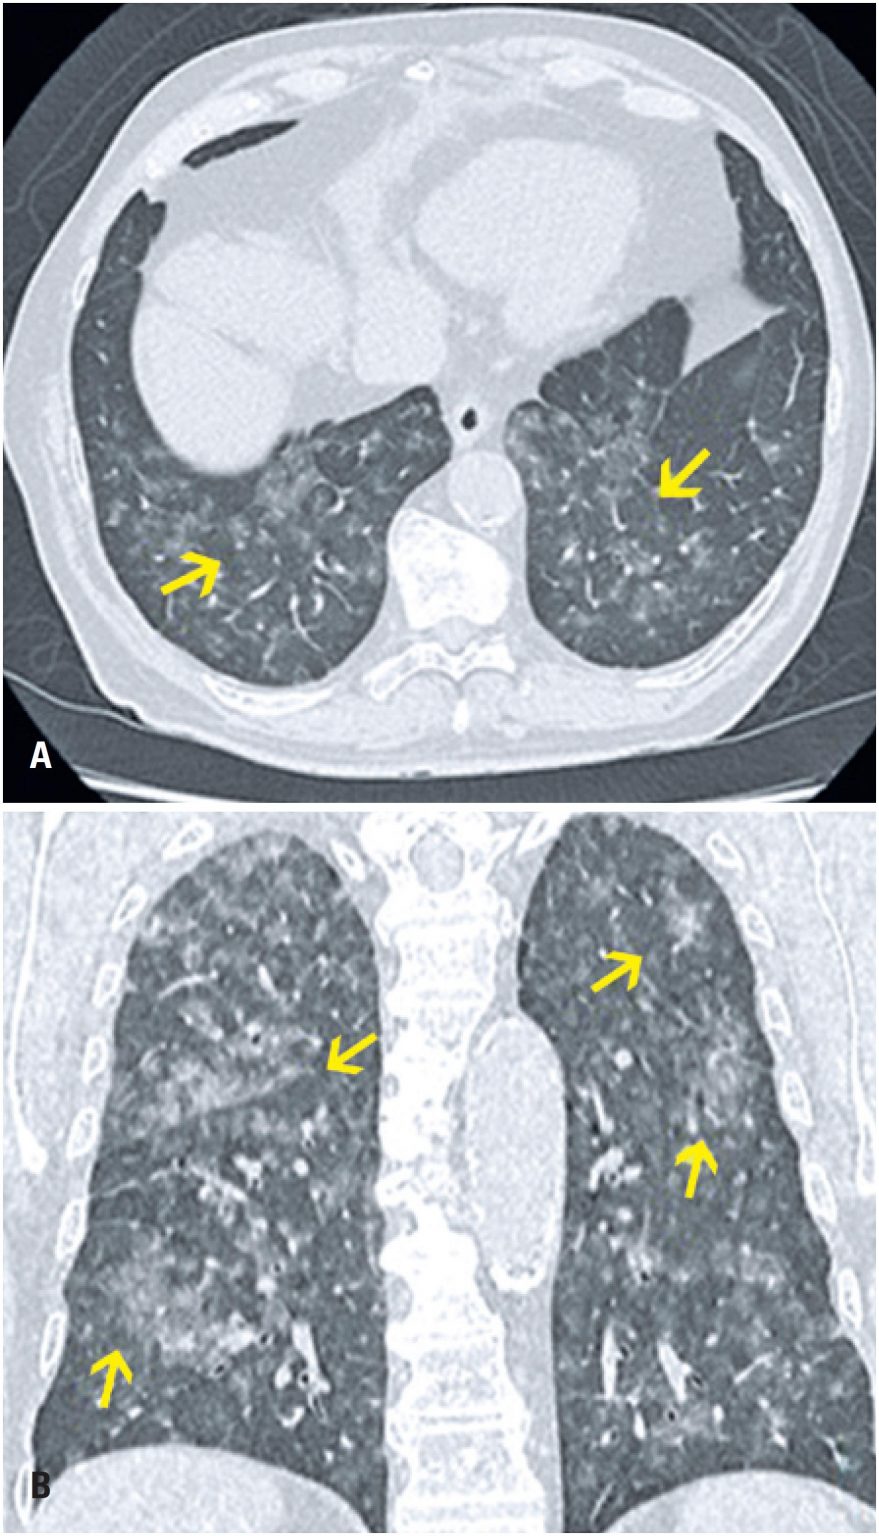

From pubs.rsna.org

Chronic Pulmonary Manifestations of COVID19 Infection Imaging Persistent Ground Glass Opacity Post Covid At 3 months after acute infection, a subset of patients will have ct abnormalities that. Residual ground glass opacities, consolidations, reticular and linear opacities, residual crazy paving pattern, melted sugar sign,. Ct scans in 73 participants after discharge (median, 105 days; Persistent Ground Glass Opacity Post Covid.